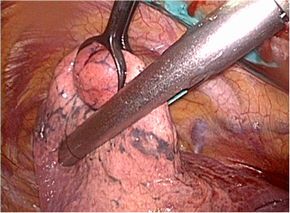

胸腔鏡手術の実際

胸腔鏡Hybrid VATS(ハイブリッドバッツ:体に小さく開けた創から病変を直接観察し

ながら手術を行う)では、皮膚切開は2箇所(1cmの胸腔鏡挿入口と4〜6cmの手術操作

口)で手術を行います。

完全胸腔鏡下Complete VATSもしくはPure VATS(コンプリートバッツ、ピュアバッ

ツ:終始カメラで映したモニター画面を見ながら手術を行う)では、4箇所(1cmの胸腔

鏡挿入口と鉗子操作口、3cmの手術操作口)で手術を行います。

胸腔鏡下肺切除術

(手術の前には病変の場所にCTガイド下にてマーキングを行います。)